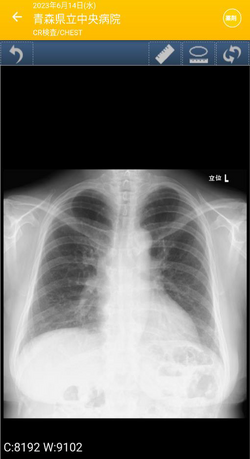

(渡部)たとえば、血液の検査結果、処方された薬、レントゲン画像、通院した日なんかを確認できます。これまでは紙で貰っていた検査データなどの内容が、アプリにまとまっている感じですね。

レントゲン写真確認画面

今回初めて「NOBORI」のアプリを見させてもらったのですが、レントゲン写真や検査結果を、アプリですぐに、何度でも確認できることに衝撃を受けました。自分のレントゲン写真、何度だって見たいですよね!(私だけかも)